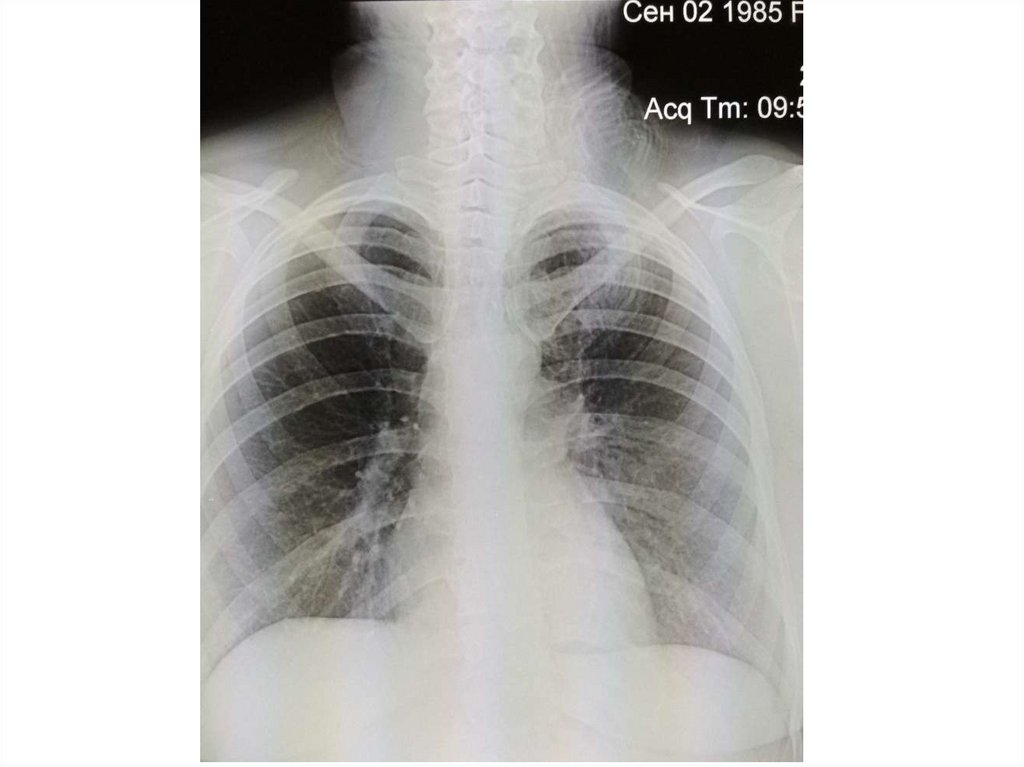

Лучевое исследование лёгких, сердца и крупных сосудов

Лучевое исследование лёгких,

сердца и крупных сосудов